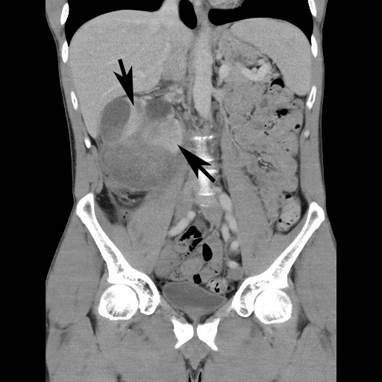

A 43-year-old Caucasian man, with a 4-week history of right upper quadrant and right flank pain radiating to his right testicle, presented to his general practitioner. There was no preceding trauma, haematuria or any other systemic symptoms. The past medical history included osteoid osteoma in the left upper femur, which was removed in 2007. He also had L4/5 microdiscectomy. There was no positive family history of medical problems or cancer. He was a non-smoker, had no allergies and was not taking any regular medications. The general practitioner organized an ultrasound, which revealed a large subcapsular haematoma measuring 7 × 5 × 7 cm in the right kidney compressing the renal cortex. Further investigation with computed tomography (CT) scan of the abdomen with intravenous contrast revealed enlarged right kidney with subcapsular haematoma and a mass lesion within the right lower pole measuring up to 7.4 × 7.5 × 9.2 cm with associated paracaval lymphadenopathy producing compression of the right renal vein and inferior vena cava (Figures 1 and 2). The patient was then referred to an urologist for further management.

Figure 1. CT scan – coronal view. Large mass lesion (arrow) within right kidney measuring up to 7.4 × 7.5 × 9.2 cm.

Figure 2. CT scan – coronal view showing right kidney mass with subcapsular haematoma (arrows).

Physical examination revealed that the right kidney area was filled, with minimal tenderness. The haemoglobin concentration was 140 g/L. There was a mild elevation of creatinine (116 μmol/L), and the estimated glomerular filtration rate was 66 ml/min. CT staging showed a large right renal tumour and significant paracaval lymphadenopathy producing compression of the right renal vein and inferior vena cava. The size of the tumour was substantially increased in size to 11.5 × 11.6 × 11.5 cm when compared with that in the previous CT scan.